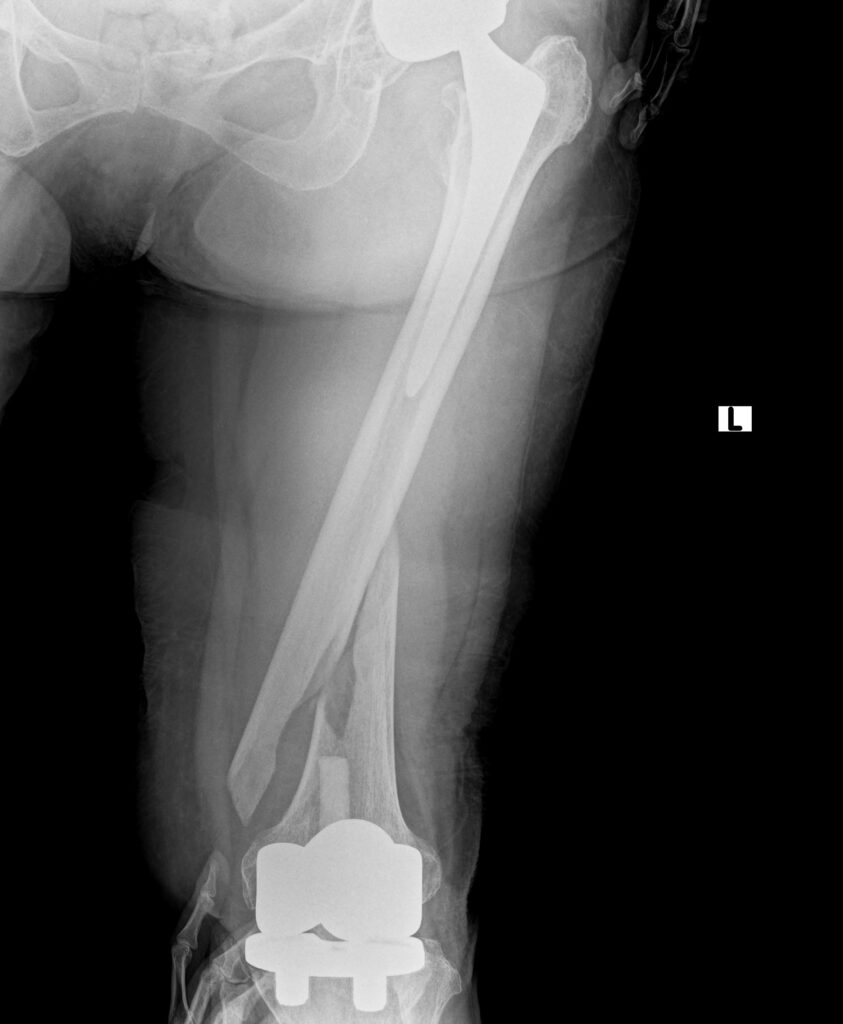

先日、左の人工股関節と左の人工膝関節手術を受けた70代の女性が、

転倒により左大腿骨骨折が生じたため手術治療を行いました。

人工股関節と人工膝関節の間で螺旋状に骨折しています。